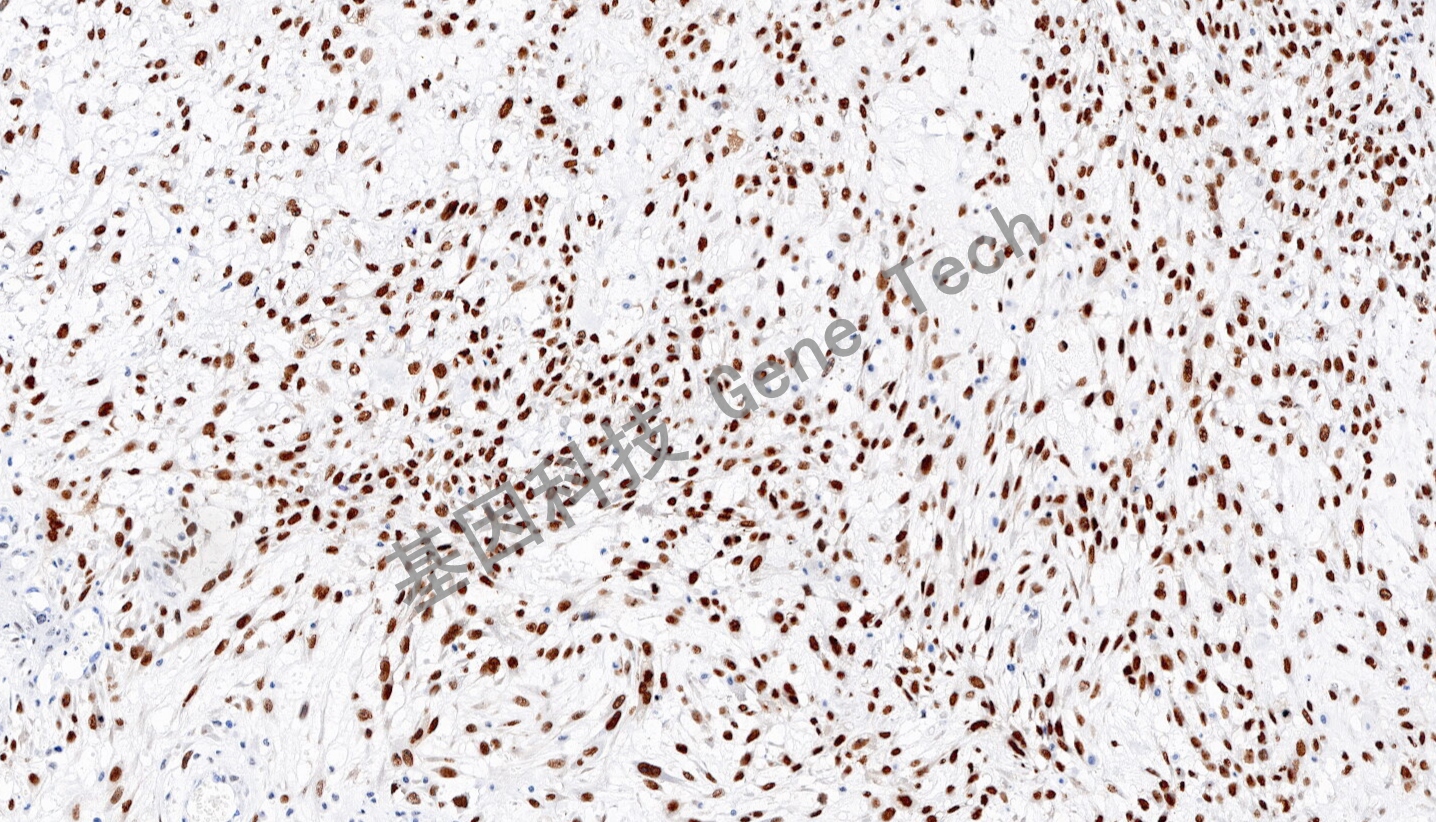

| 骨肉瘤石蠟切片,用 RUNX2(GT2586)染色,細(xì)胞核陽性,DAB 顯色。 | ||

| 預(yù)處理:高pH熱修復(fù) | 陽性部位:細(xì)胞核 | 陽性對照:骨肉瘤 |